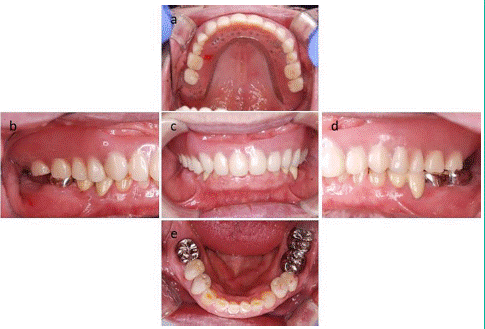

Radiographic examination revealed root fractures in teeth 15 and 27 (Figure 1a and 1b).

Figure 1: Preoperative radiographs. A) Radiographic image of the maxillary right molars. The yellow arrow indicates root fracture. B) Radiographs of the left maxillary molars. The yellow arrow indicates root fracture.